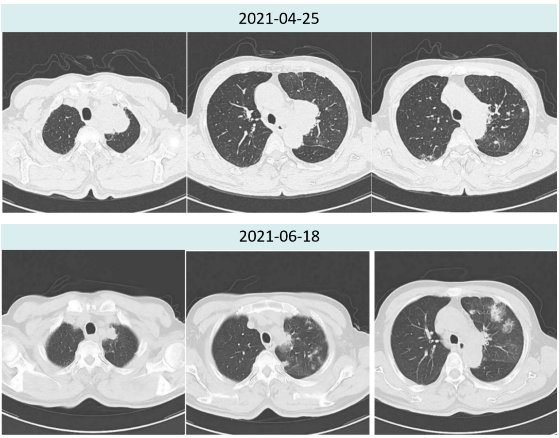

2021年6月18日治疗两周期后复查胸部CT提示:肿瘤较前明显缩小(4.5cm→2.0cm),新增多发炎性病灶,总体疗效评价为PR。

图1.患者治疗前后胸部病灶对比